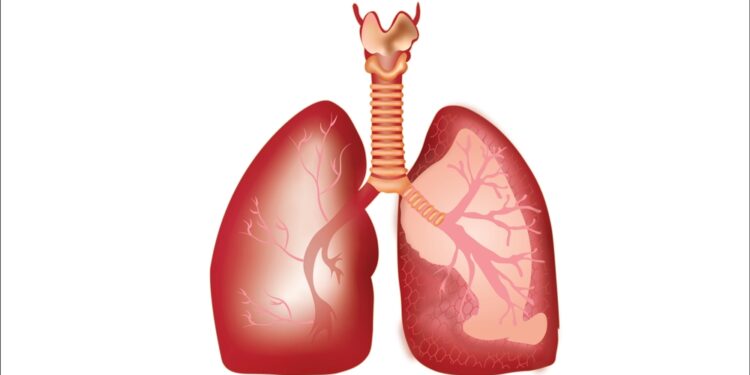

- Plaučio subliūškimas (pneumotoraksas) – oras tarp šonkaulių ir plaučio

- Pleuros uždegimas – plaučius dengiančių membranų uždegimas

- Plaučių embolija – kraujo krešulys plaučių arterijoje

- Plaučių hipertenzija – aukštas spaudimas plaučių kraujagyslėse